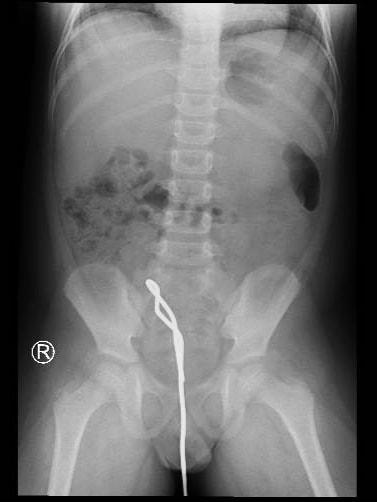

Thanh sắt nằm trong bụng bệnh nhi qua chẩn đoán hình ảnh. Ảnh BVCC